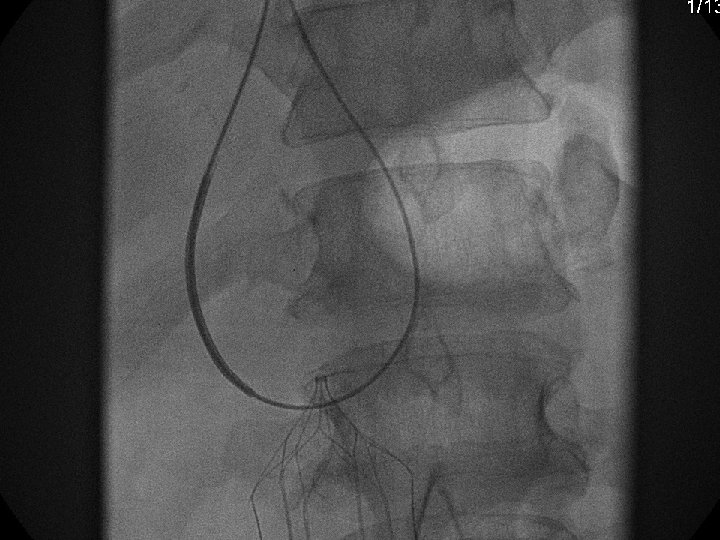

Snare Retrieval En. Snare

Recovery (G 2) Retrieval

Removal of an “Intravascular Foreign Body” Straight forward Loop snare Grasping device Complex Multiple devices used including angioplasty balloons, bronchoscopy forceps, and the“in situ” snare technique.

Retrieval with a snare and a long sheath or guiding catheter Günther Tulip (Cook) Celect (Cook) Opt Ease (Cordis Endovascular) Option (Angiotech) G 2 X, Eclipse, Meridian (Bard)